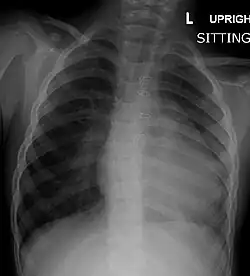

Chest radiograph

Before more sophisticated techniques became available, chest X-ray was the definitive method of diagnosis. The abnormal "coeur-en-sabot" (boot-like) appearance of a heart with tetralogy of Fallot is classically visible via chest X-ray, although most infants with tetralogy may not show this finding.[50] The boot like shape is due to the right ventricular hypertrophy present in TOF. Lung fields are often dark (absence of interstitial lung markings) due to decreased pulmonary blood flow.[51]: 171–172

Right ventricular hypertrophy | The right ventricle is more muscular than normal, causing a characteristic boot-shaped (coeur-en-sabot) appearance as seen by chest X-ray. Due to the misarrangement of the external ventricular septum, the right ventricular wall increases in size to deal with the increased obstruction to the right outflow tract. This feature is now generally agreed to be a secondary anomaly, as the level of hypertrophy tends to increase with age.[45] |